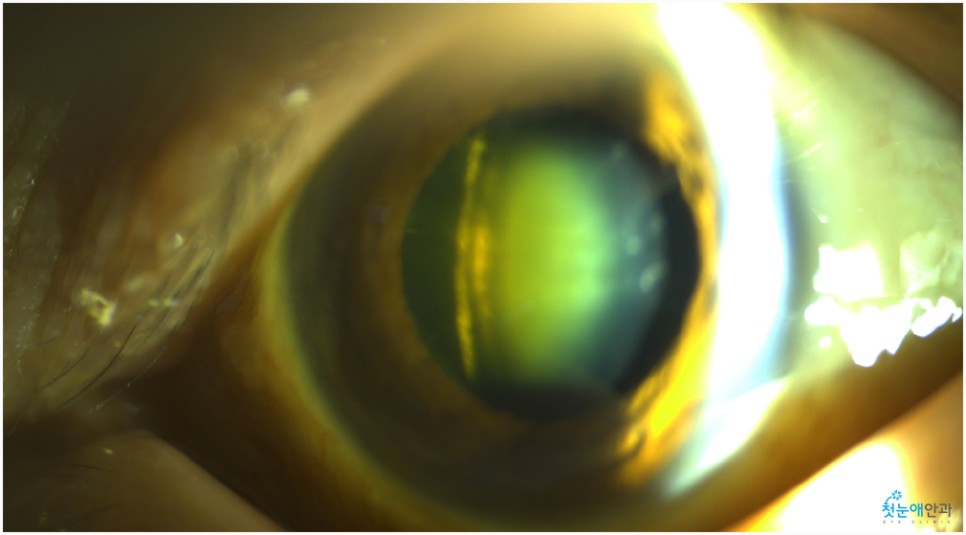

노안 수술 안과에 내원하셨을 때 오른쪽 눈이 잘 보이지 않는다고 말씀하셨습니다.이에 첫눈 애안과 장비를 통해 조사한 결과 이미 백내장 진행이 상당하고 눈 밑 망막 관찰이 어려울 정도로 흐릿한 상태였습니다.

눈이 침침해서 잘 보이지 않았던 것은 올해 초부터라고 말씀하셨습니다.진단 결과 백내장 B) N5CO(+++) PSC(+++) 단계에 해당되며 이는 매우 심한 정도여서 예전에는 맑은 수정체였으나 지금은 혼탁하고 진한 갈색으로 바뀌었습니다.참고로 백내장 초기라면 약물 사용으로 진행을 늦출 수 있었을 것 같은데, 노안수술안과를 방문해주신 환자들은 너무 많은 진행이 있었기 때문에 수술이 필요했습니다.

백내장이 상당히 진행되면 수정체가 흐려져 눈 아래의 망막 관찰이 어렵습니다.때문에 사진을 찍어 검사해봐야 하는데 위와 같이 흐릿한 사진이 찍혀 사실상 망막 관찰이 어렵습니다.뿐만 아니라 심한 백내장은 부분마취 수술 진행이 어려워 안구마취나 전신마취로 수술하거나 종합병원으로 전환해 수술해야 합니다.뿌옇게 변했는데도 그냥 놔두면 위 사진처럼 더 심해져 시력이 저하되는 상황까지 이어지게 됩니다.